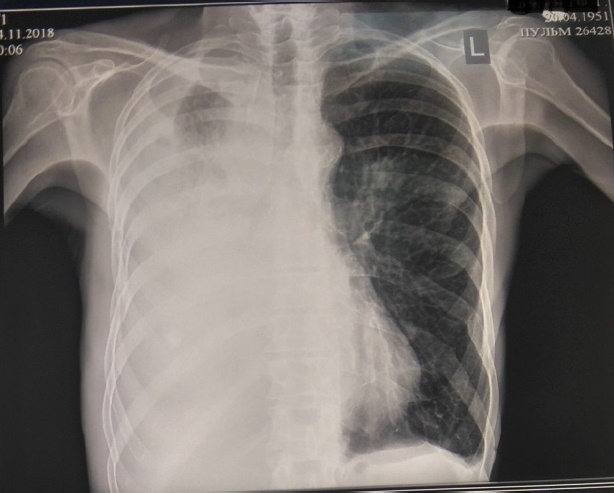

Рентгенография от 27.08.2018 и мультиспиральная компьютерная томография (МСКТ) органов грудной клетки и брюшной полости от 03.09.2018 – определяются признаки гиповентиляции средней доли легкого с застойными изменениями по типу инфильтрации. МСКТ грудной клетки от 07.09.2018: прикорневой инфильтративный процесс с переходом на среднюю долю справа, выраженный пневмофиброз с обеих сторон. Малый гидроторакс справа. Внутригрудная, внутри- и забрюшинная лимфоаденопатия. Фиброзные изменения верхушки. Бугристая деформация почек, утолщение стенки желудка, спленомегалии (рис. 1).

Рис. 1. МСКТ органов грудной клетки и брюшной полости от 03.09.2018